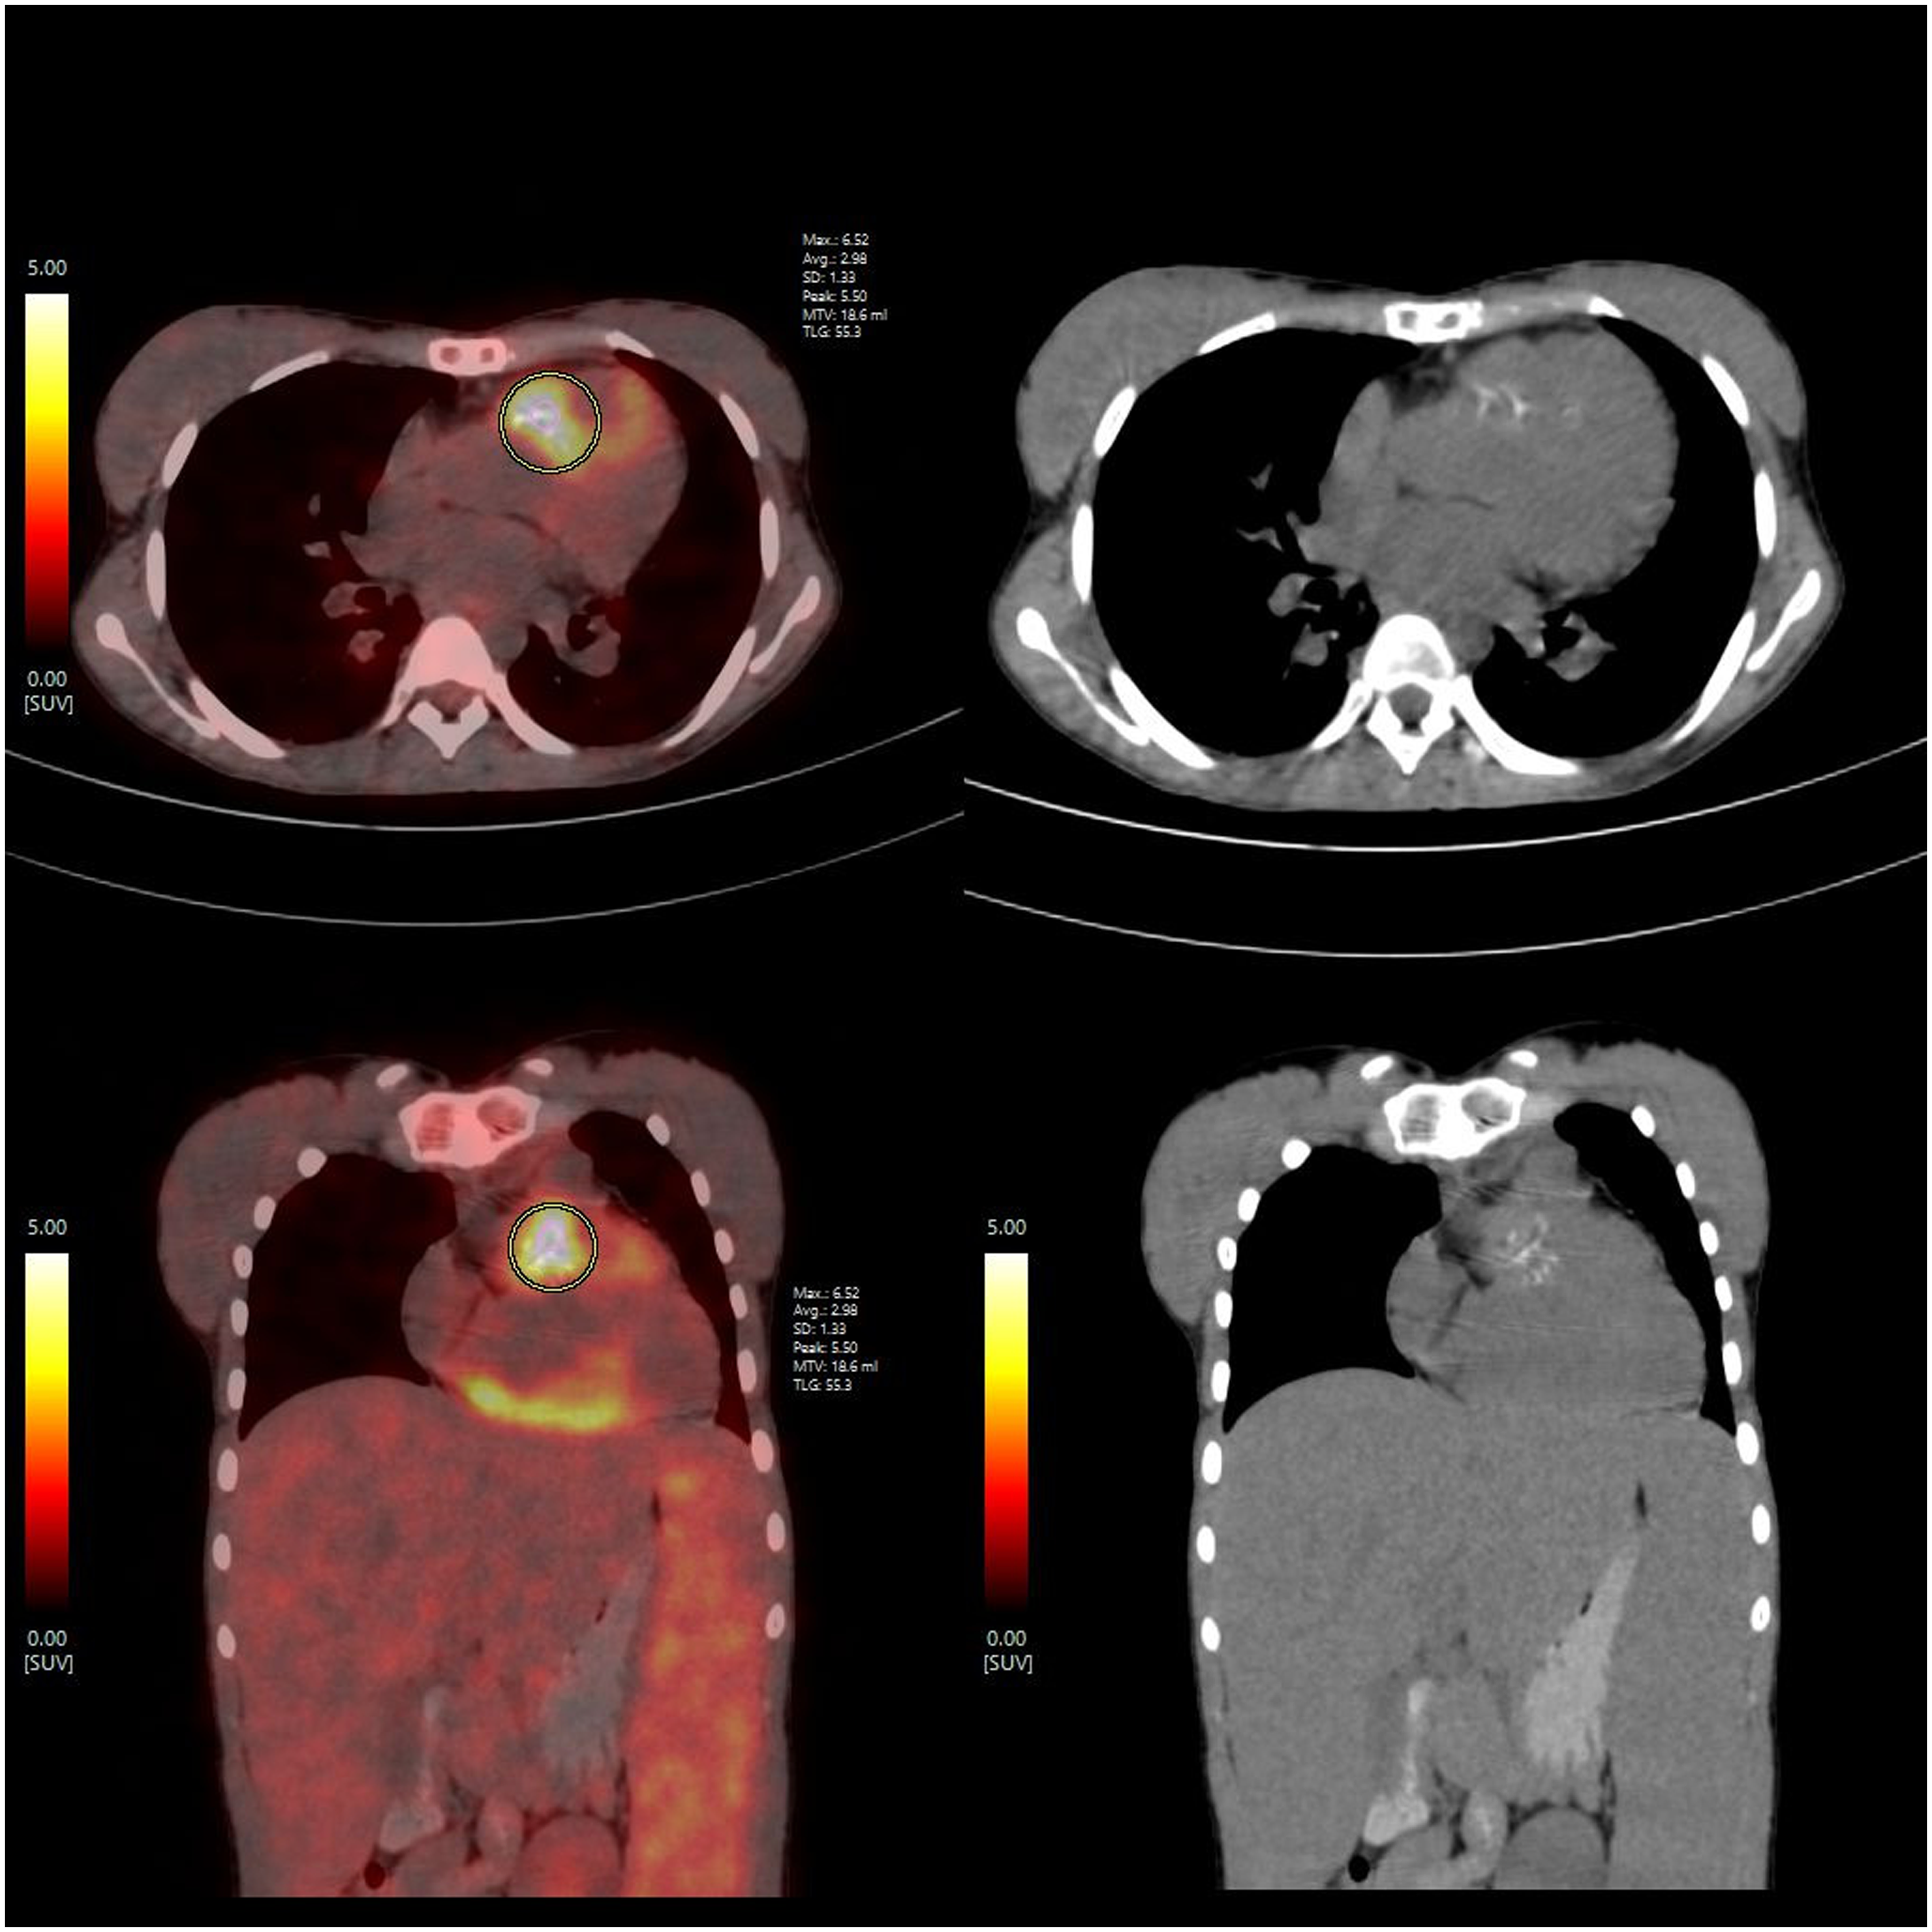

Investigations showed severe anaemia with a haemoglobin of 6.8 gm%. Although her total lymphocyte count (8200 per mm3) was normal, the markers of inflammation, such as erythrocyte sedimentation rate 70 mm/hour and C-reactive protein 114mg/dL, were elevated, suggesting infection. Rheumatoid factor was negative and urine analysis showed 12 pus cells and 4 red blood cells per high power field and proteinuria of 180 mg/dl in 24 hours sample. Work-up for cause of anaemia revealed an elevated lactate dehydrogenase 457 IU/L and indirect hyperbilirubinemia. Blood cultures sent from three sites grew gram-negative bacilli-Burkholderia cepacia sensitive only to ceftazidime, minocycline, and levofloxacin. Thus, suspecting IE an echocardiography was performed, which showed a large mobile pedunculated mass attached to the pulmonary valve with degeneration of the valve leaflets causing severe right ventricle outflow tract obstruction with peak systolic gradient of 90 mm Hg (figure 1). The surgical patch was intact. Whole body positron emission tomography showed high-grade uptake in patch area near pulmonary valve and subjacent right ventricular myocardium with small consolidatory areas of uptake in bilateral lower lung lobes suggesting septic pulmonary embolism (figure 2).

Figure 2. Whole body FDG-PET-CT image showing increased uptake in right ventricle outflow tract and subjacent myocardium.

The current European Society of Cardiology Guidelines for diagnosis and management of infective endocarditis give a Class IA recommendation to Flurodeoxyglucose positron emission tomography (FDG-PET) as a modality to detect peripheral lesions in symptomatic patients. Our patient showed involvement of surgical patch and surrounding myocardium as well as septic pulmonary embolism. There was no evidence of systemic embolism. Reference Delgado and Ajmone Marsan5 Intravenous antibiotic therapy in accordance with the culture report remains the cornerstone for management of all cases of endocarditis. Specific indications for surgery, especially in right heart involvement, include difficult to eradicate organisms, large vegetations (≥1 cm), right-sided heart failure, persistent bacteraemia despite adequate anti-microbial therapy, recurrent pulmonary emboli, and intramyocardial abscess. Reference Shmueli, Thomas and Siegel1